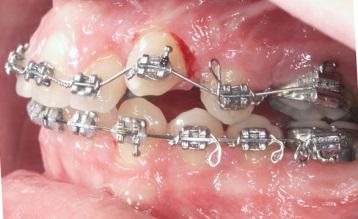

Les arcs orthodontiques

Les arcs orthodontiques moteur de l’appareillage sont au début du traitement de faible diamètre et très élastiques délivrant des forces légères, le matériau est le titane . Les diamètres des fils et leur rigidité augmentent dans les phases suivantes . Le fil est change une fois qu’il a délivré son action , les progrès en metallo-technie permettent de laisser les fils orthodontiques plus longtemps sans perte d’efficacité .